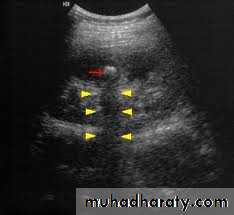

Ultrasound findings

1-Dilatation of the P.C.S. appears as multilocular fluid collection within central echo complex.

-With more severe distention, dilated calyces appear as

Multiple cysts but communicating with each other unlike true cysts.

-Proximal and distal ureteric dilatation can be easily identified unlike mid-ureteric dilatation, and stones located in the middle third of the ureter are hard to be demonstrated unlike upper and lower ureteric stones (especially those lodged in the vesico-ureteric junction or pelvi -ureteric junction) which are easily identified by ultrasound.